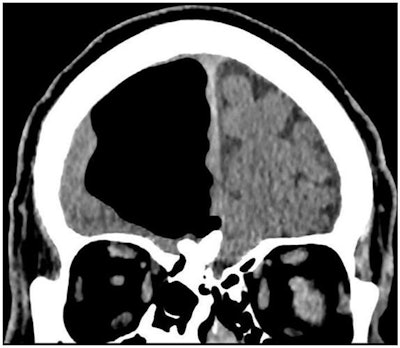

Clinicians in Northern Ireland reported that CT scans of a patient revealed a sizable black spot in the frontal lobe of the brain. This hypodense mark turned out to be a pocket of air that was compressing brain tissue as it seeped into the skull, according to a paper in BMJ Case Reports.

Hoping to clarify the cause of the man's symptoms, the researchers turned to imaging. They acquired CT scans of the brain and found a 3.5-inch air-filled cavity, or pneumatocele, within the patient's right frontal lobe (BMJ Case Rep, February 27, 2018). Additional MR images of the head corroborated that the hypodense spot was, indeed, an air pocket and also uncovered an osteoma and signs of acute ischemia nearby.

Collectively, the findings suggested that the osteoma had gradually eroded the bone plate near the nasal cavity enough to allow air to enter the right frontal lobe in a "one-way valve effect."